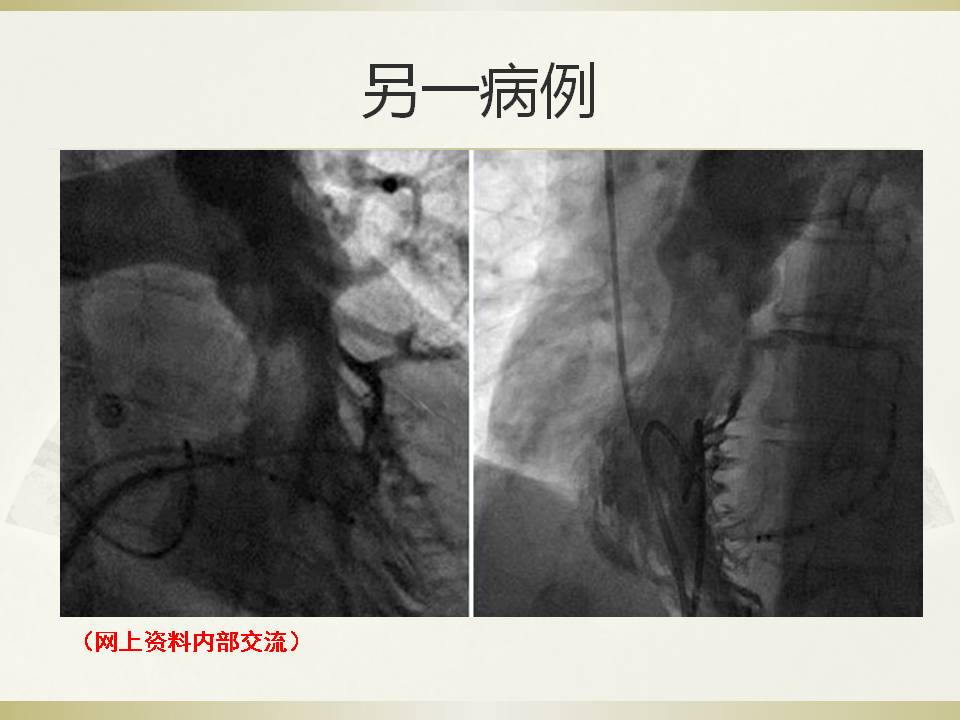

房速1例的射频消融

雷森 何泉